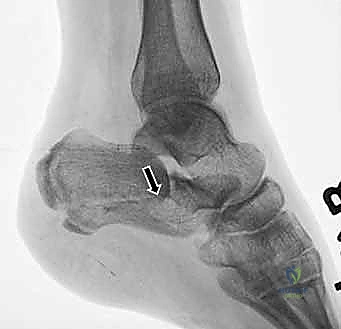

4. التثبيت المؤقت

يتم استخدام أسلاك معدنية دقيقة لتثبيت الشظايا في مكانها مؤقتاً، ثم يتم التحقق من دقة الرد باستخدام جهاز الأشعة السينية داخل غرفة العمليات (C-arm) لضمان عدم وجود أي انزياح ولو بمليمتر واحد.

5. التثبيت النهائي باستخدام الشرائح والمسامير (Plating)

يتم وضع شريحة تيتانيوم (Titanium Plate) مصممة خصيصاً لتطابق الشكل التشريحي لعظم الكعب. يتم تثبيت هذه الشريحة بمسامير قوية لتوفير ثبات ميكانيكي صلب يسمح بالالتئام السليم ويمنع انهيار العظم مرة أخرى. في بعض الحالات التي يوجد فيها فراغ عظمي كبير، قد يستخدم الدكتور هطيف طعوماً عظمية (Bone Grafts) لملء الفراغ.